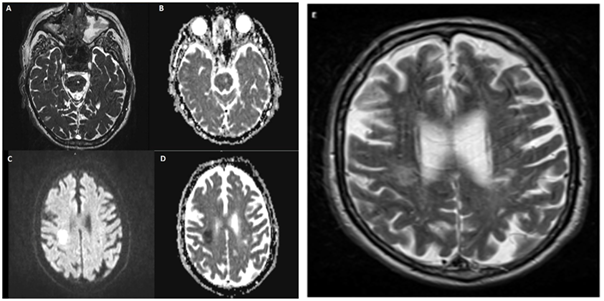

CT and MRI scans revealed an AIS in the right posterior frontal cortex (Figure 2C, 2D & 2E). Originally a left tegmental enhanced lesion was overlooked as a non-specific focus of signal prolongation which was interpreted as small vessel disease (Figure 2A & 2B). There was no other acute infarct identified on MRI, as well as the MRA was non-contributory.

Figure 2 A & B. Axial T2 and ADC showing signal changes in the left cerebral peduncle, ventrolateral pontine tegmentum region, this signal prolongation is characteristic of microagniopathic ischemia. C, D & E; DWI, ADC & T2 images demonstrating restricted diffusion in the right frontoparietal centrum semiovale region suggesting a focal a focal non-hemorrhagic infarct A: T2, B: ADC, C: DWI, D: ADC, E: T2.